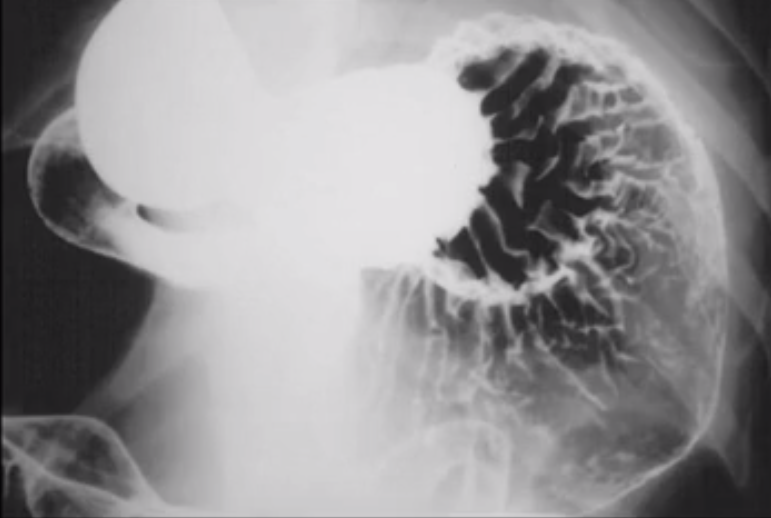

What does this image show?

Normal dog stomach mucosa using double contrast gastrogram